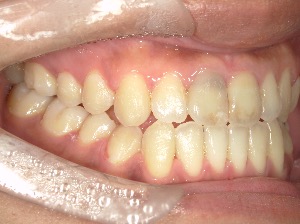

before

after

患者さんの年齢 20代 女性 症状 ガタガタを治したい 治療内容 マウスピース矯正治療 費用 90万(税抜) 治療期間・回数 治療期間2年、通院回数10回 メリット 笑顔が綺麗 デメリット・リスク 期間がかかることがある - マウスピース矯正